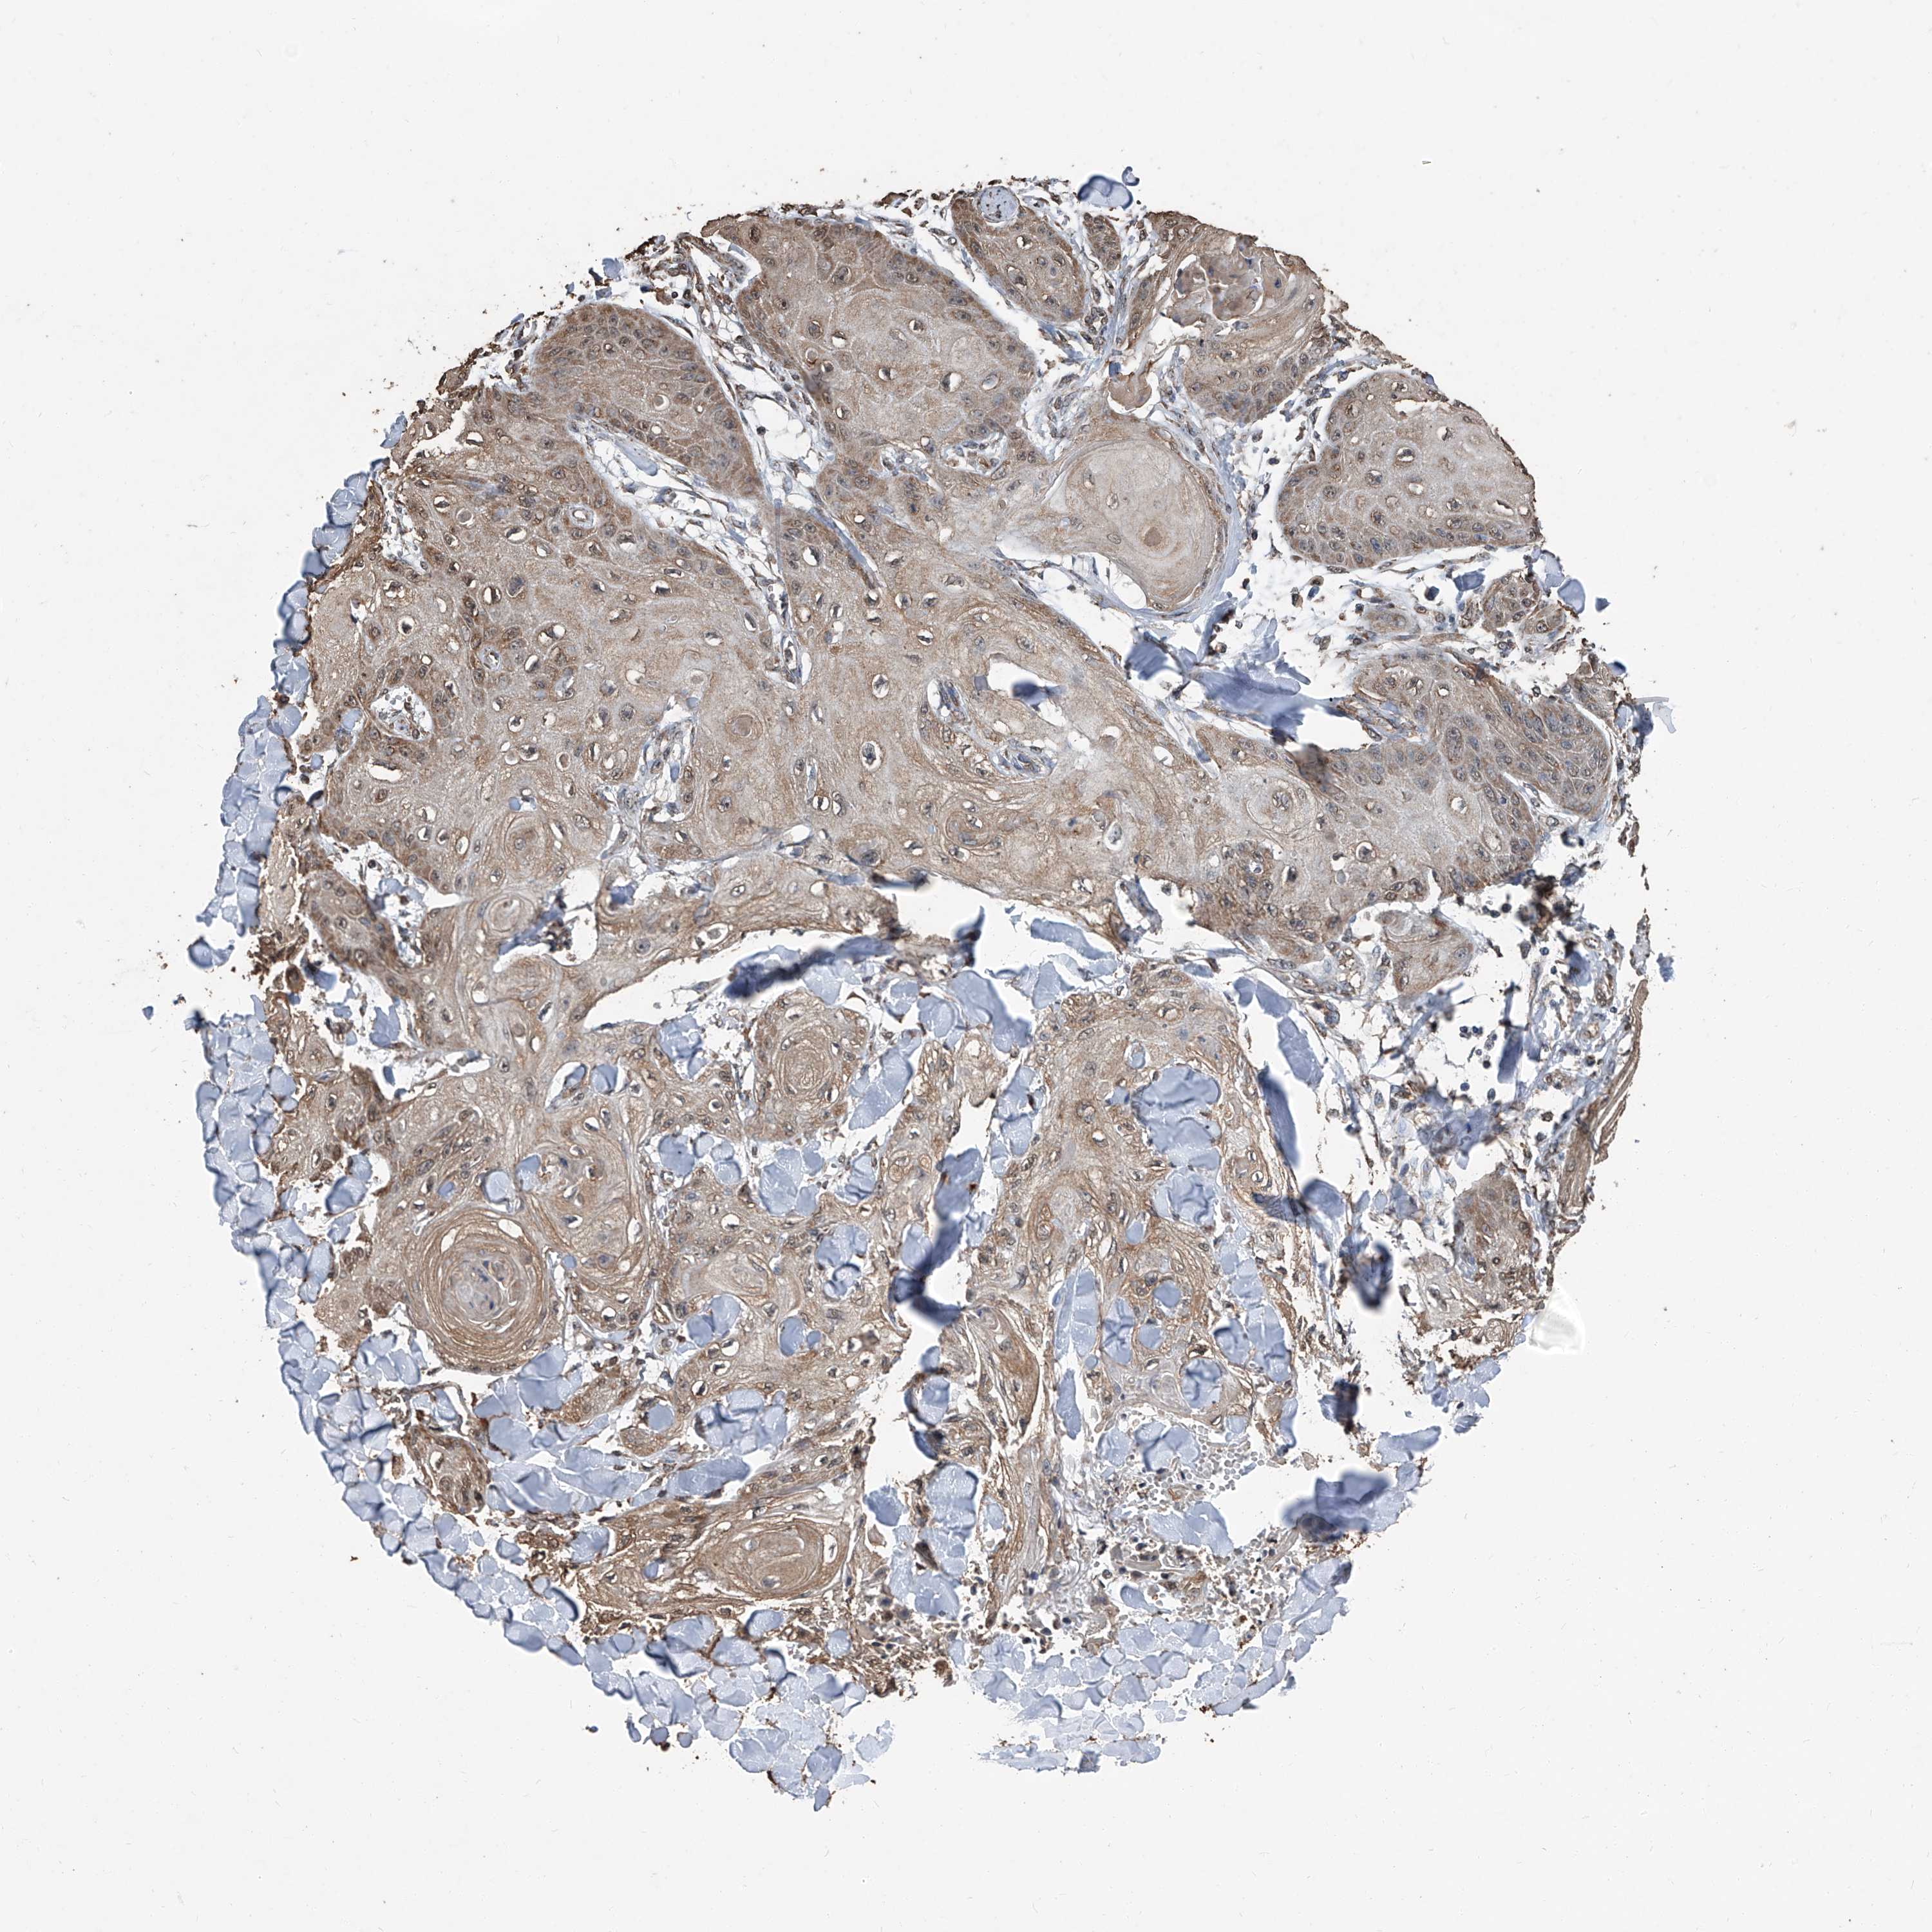

SKIN CANCER - Protein expressioni

A mouse-over function shows sample information and annotation data. Click on an image to view it in a full screen mode. Samples can be filtered based on level of antibody staining by selecting one or several of the following categories: high, medium, low and not detected. The assay and annotation is described here.

Antibody staining in the annotated cell types in the current human tissue is reported as not detected, low, medium, or high, based on conventional immunohistochemistry profiling in selected tissues. This score is based on the combination of the staining intensity and fraction of stained cells.

Each image is clickable and will lead to virtual microscopy that enables deeper exploration of all samples and also displays staining intensity scores, fraction scores and subcellular localization as well as patient and tissue information for each sample.

Antibody CAB033965

Basal cell carcinoma

Squamous cell carcinoma, NOS